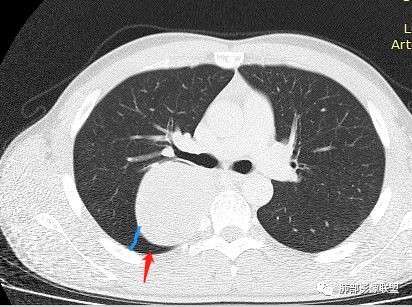

长沟流月去无声:

这根看强化

是体循环供血

脏层胸膜主要由支气管动脉和肺动脉供血,壁层胸膜主要由支气管动脉,胸廓内动脉、肋间动脉供血

如果是肋间动脉,就不可能是脏层胸膜,可以是壁层或者纵膈

但是这个病人,肋间动脉供血吧,我倾向胸膜

看血供来源(体循环),脏层来源需要打个问号了

肋间动脉供血,强化尚均匀,逐步强化

供血,体外供血,体循环,要么是壁层胸膜,要么胸膜外的,脏层胸膜应该是对内供血。病变里面的血管,除非是非常粗大迂曲的血管,不然,我不认为是其特点。

脏层胸膜肺内供血,壁层胸膜体外供血

这个病人不是肺动脉与支气管动脉供血,是肋间动脉供血